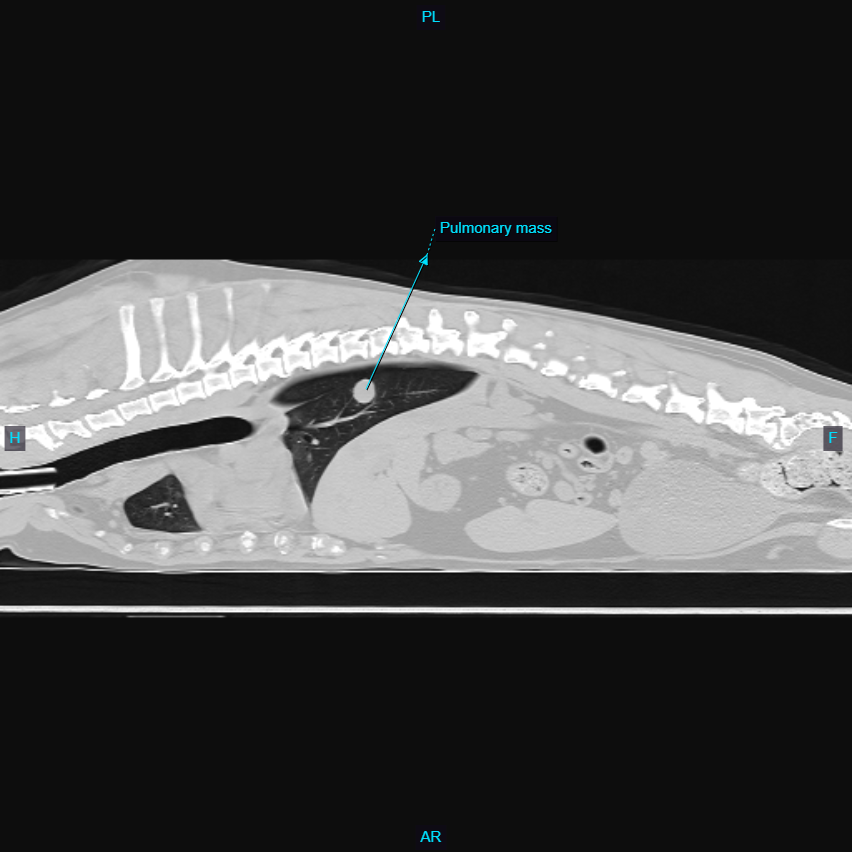

Oakley is now an 11 yo FS Lab. She presented in November for a splenic mass and suspected metastatic lung nodule. She was asymptomatic at home, other than she had vomited once and not eaten well for a few days. She presented through outpatient ultrasound with Dr. Sepulveda, who identified a splenic mass. Radiographs of the chest were taken, and found one solitary, approximately 2cm mass in the right caudal lung field, but no other changes. While it could have been a spread from the splenic mass, typically, we see more than one nodule, especially at 2cm in size. The owner wanted to give her every chance, so a CT was performed immediately before surgery, where just one nodule was confirmed (see pic – one of pulmonary nodule, one of splenic mass). She was taken to surgery with Dr. MacDougall and her spleen was removed, with biopsy results coming back about a week later as a myelolipoma, which is not cancer! The owner elected at first to monitor the nodule in her chest (in the accessory lung lobe). Radiographs taken about 3 months later showed about 50% increase in this pulmonary nodule, but no additional nodules or changes in her lung. The owner elected to allow Dr. MacDougall to take the lung nodule out via right lateral thoracotomy (removal of accessory lung lobe), and a grade 1 pulmonary carcinoma (removed with clean margins) was found on biopsy. This can potentially spread over time, but her prognosis is good. The owner was thrilled at her second chance at life, since she is in excellent health and still loves to walk, swim, and play. She is one of our perfect patients!